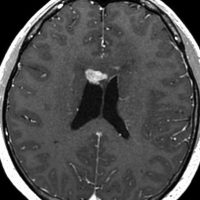

ICEを3コース行なって腫瘍は完全消失して,前頭葉浮腫も消えました。その後に,全脳照射 25.2Gy/14分割を加えました。無症状で復職することができました。